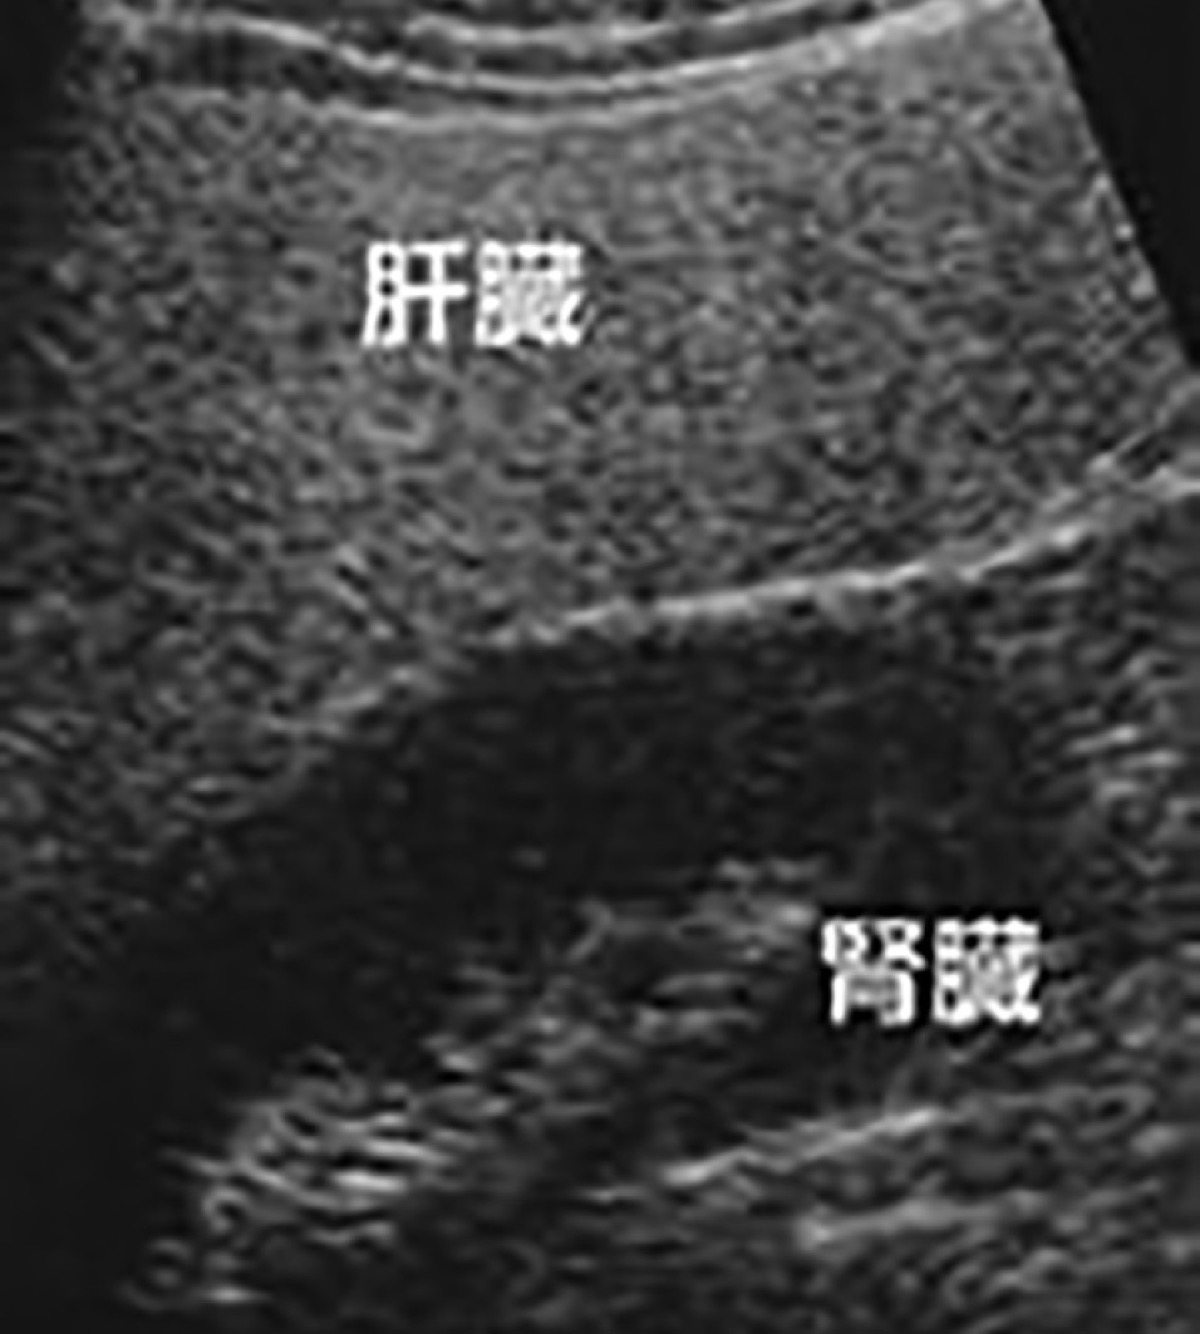

「飲酒の習慣がなく、過去に行った肝炎ウイルス検査でも異常がなかったので大丈夫だと思っている人が少なくない」と徳永教授。メタボリックシンドロームの言葉の広まりとともに近年、脂肪肝が大きな関心を集めている。軽度肝機能数値異常者の中には、脂肪肝が含まれており、過去に腹部超音波で脂肪肝と診断されたことがある人は多いはずと指摘。そうした症状を抱える人たちは、肝臓が徐々に硬くなってくるため、その予兆を察知することが重要になるという。

徳永教授によれば「採血でもある程度判るが、最先端の腹部超音波を用いることで肝臓の線維化がより正確に把握できるようになった」とのことで、同院ではこれが可能な検査機器を導入している。メタボ気味の人、過去にメタボと診断された人、肝機能の数値がわずかでも高い人、過去に超音波などで脂肪肝と診断された人などを対象に検査を行っている。